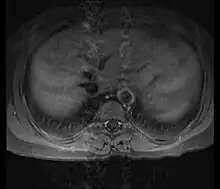

Although the cause of Takayasu arteritis is unknown, the condition is characterized by segmental and patchy granulomatous inflammation of the aorta and its major derivative branches. This inflammation leads to arterial stenosis, thrombosis, and aneurysms.[4] There is irregular fibrosis of the blood vessels due to chronic vasculitis, leading to sometimes massive intimal fibrosis (fibrosis of the inner section of the blood vessels).[6] Prominent narrowing due to inflammation, granuloma, and fibrosis is often seen in arterial studies such as magnetic resonance angiography (MRA), computed tomography angiography (CTA), or arterial angiography (DSA).

Diagnosis is based on the demonstration of vascular lesions in large and middle-sized vessels on angiography, CT scan, magnetic resonance angiography or FDG PET.[12] Seeing abnormal diffuse arterial wall thickening, the 'macaroni sign', with ultrasound is highly suggestive of the condition.[13] FDG PET can help in diagnosis of active inflammation not just in patients with active Takayasu arteritis prior to treatment but also in addition in relapsing patients receiving immunosuppressive agents.[5][14]

Contrast angiography has been the gold standard. The earliest detectable lesion is a local narrowing or irregularity of the lumen. This may develop into stenosis and occlusion. The characteristic finding is the presence of "skip lesions," where stenosis or aneurysms alternate with normal vessels. Angiography provides information on vessel anatomy and patency but does not provide information on the degree of inflammation in the wall.[12]